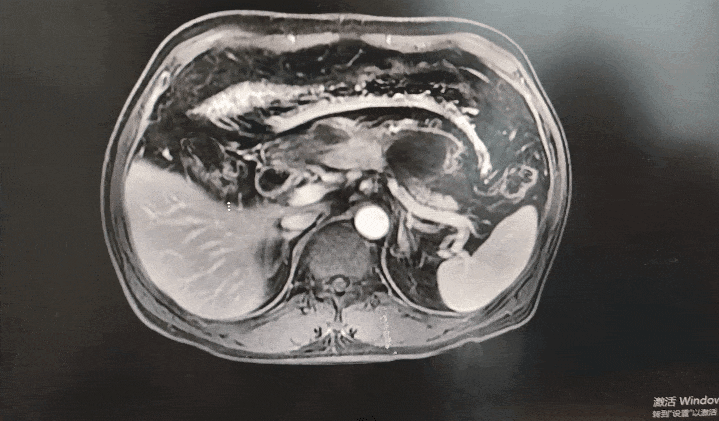

◈ 2022-11-28,TTFields联合化疗治疗2个月,上腹部MR增强扫描,对比基线( 2022-09-13):胰周多发囊性病变,考虑为术后改变(活检后),假性囊肿形成可能,较前略吸收;局部与邻近胃壁分界不清,左侧门脉高压,胃底、肠系膜静脉曲张,脾静脉近段较前显示清楚,肠系膜上动脉、腹腔干近段及局部分支周围软组织影较前范围缩小。

2022-11-28上腹部MR增强扫描—TTFields联合化疗治疗两个月